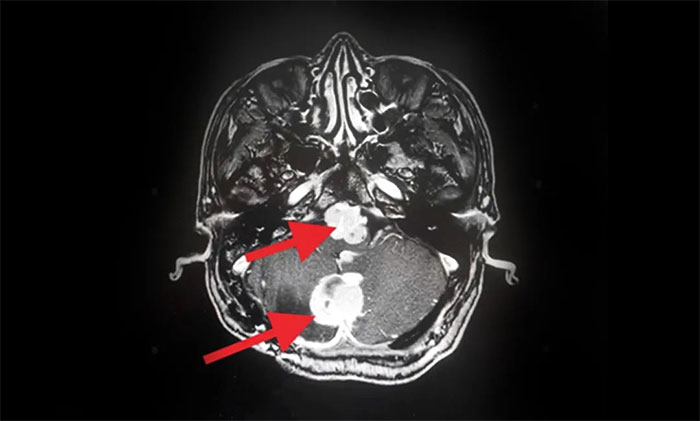

2019年,出现头痛等症状后再次就医。查头颅MRI提示:多发性脑肿瘤,考虑小脑血管母细胞瘤术后复发,基因检测提示VHL(Von Hippel-Lindau,希佩尔- 林道综合征),后采取保守治疗。

▲ MRI影像提示多发脑肿瘤

入院后,肿瘤科(放疗)头部伽玛刀组主任陈琦为他完善了MRI检查,明确多处肿瘤的位置、体积(单体肿瘤最大直径约2.7cm)。经与神经外科、医学影像科等开展MDT多学科联合会诊,评估复发肿瘤病灶毗邻脑干等重要功能区,手术难度高、风险大,可通过头部伽玛刀治疗,控制肿瘤生长,快速缓解临床症状。